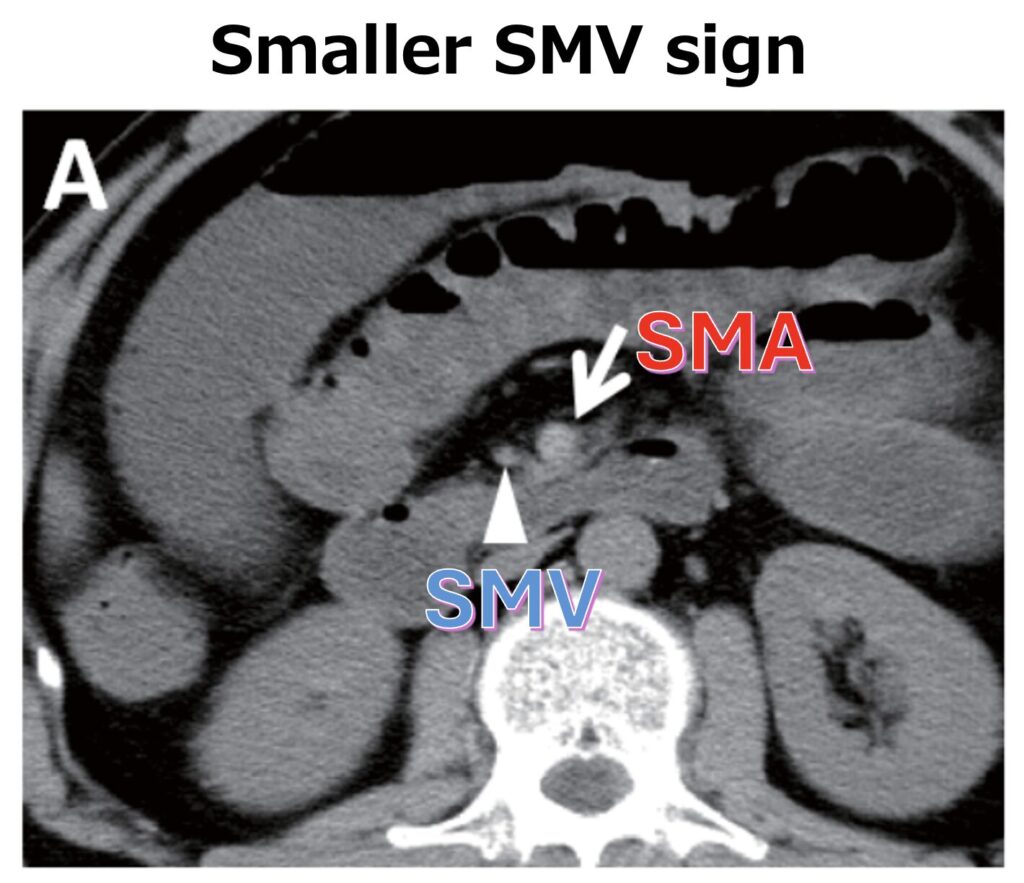

4. 上腸間膜動脈・静脈の径に注目する(血管の狭小化)

- 血管自体の閉塞がなくても、血管の攣縮によるSMA(上腸間膜動脈)の狭小化(径の縮小)や、smaller SMV sign(上腸間膜静脈が動脈よりも細くなるサイン)が認められることがあり、診断の決め手になることがあります。ただし、これらのサインの頻度は必ずしも高くなく、非特異的であることにも留意が必要です。

■smaller SMV signはなぜ生じるのか

SMA領域の循環血液量が低下すると、そこから戻ってくる静脈血(SMVの還流量)も減少します。このとき、壁の薄い静脈(SMV)は血流低下によって潰れて断面積が小さくなりますが、壁の厚い動脈(SMA)は潰れにくいため、このような径の逆転が生じます。つまり、この所見はSMA領域の循環血液量が減少していることを示す徴候として知られています。

この所見は、NOMI(非閉塞性腸管虚血)の読影において注目すべきポイントの一つですが、SMA塞栓症や広範な絞扼性イレウスなどでも認められることがあるため、NOMIに特異的な所見ではありません。

また、実際にNOMIの症例においてこのサインが認められる頻度は低いと考えられています